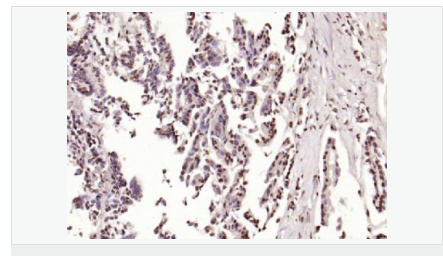

產品應用ELISA=1:5000-10000 IHC-P=1:100-500 IHC-F=1:100-500 Flow-Cyt=1μg/Test ICC=1:100 IF=1:100-500 (石蠟切片需做抗原修復)

image.png